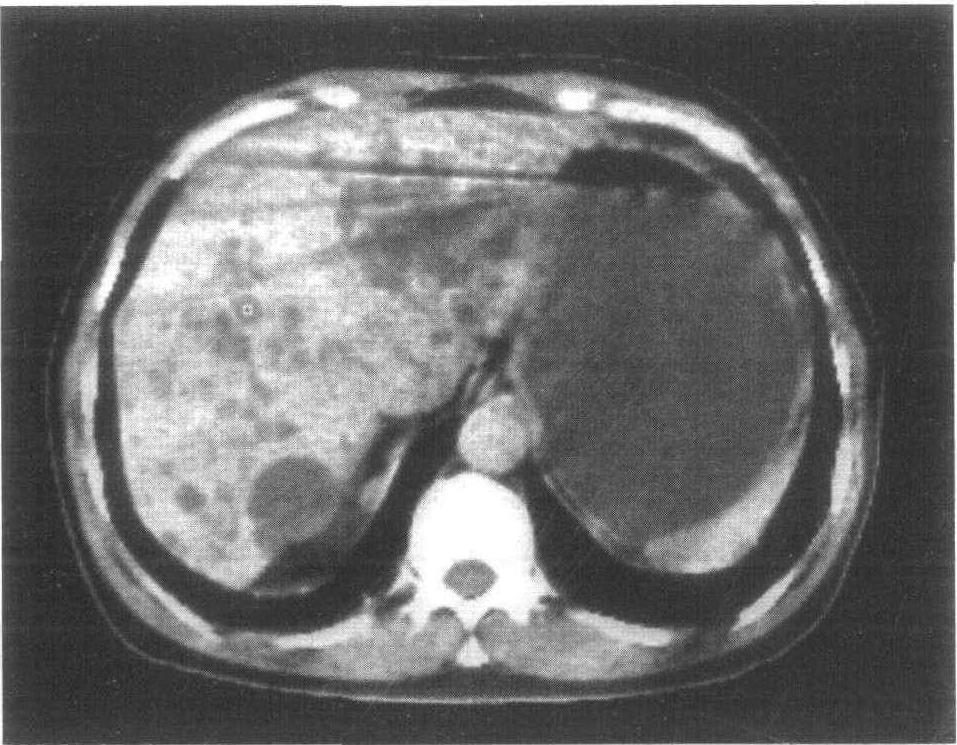

大部分肝囊肿患者,只有少数几个囊肿,但有少数病人,有多囊性肝病的情况,数目可达数十甚至数百颗,其中部分患者会因为囊肿较多而转变为慢性肝病,这时候就可能出现肝功能障碍,所以多囊性肝病患者必须做好定期复查工作。

在超声波下,肝囊肿看起来像是一个黑色、有着一层薄壁的病灶,CT上看起来则是呈现较周围肝组织黯淡的病灶,即使注射了显影剂,也没有显影变亮的迹象;但在核磁共振扫描下,肝囊肿看起来非常亮,像是一个小灯泡,这是一个很具诊断性的特征。